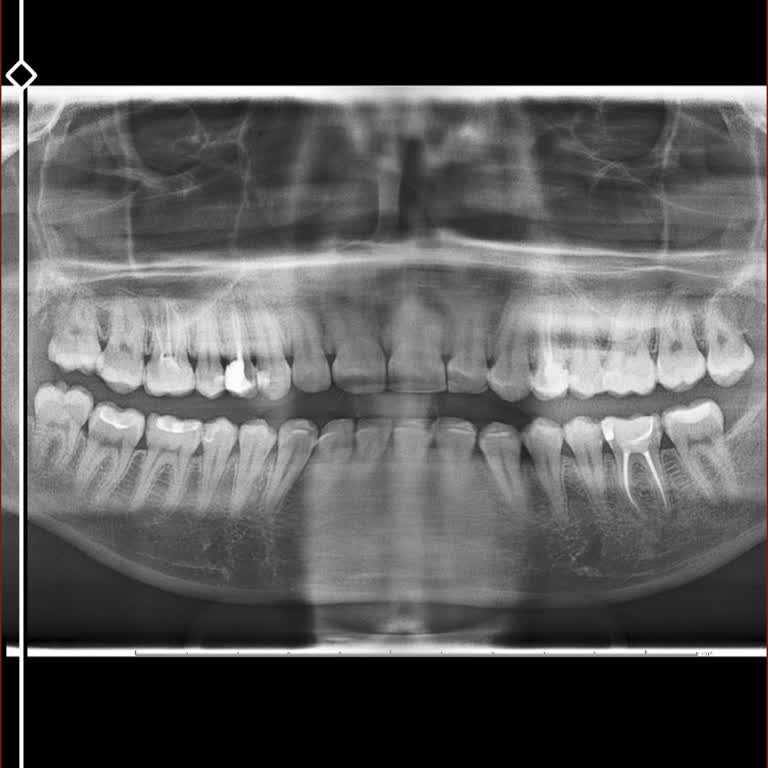

16 Şubat 2026 tarihinde İnegöl Ağız ve Diş Sağlığı Hastanesi’nde Dr. H**’e muayene oldum. Hamilelik düşündüğümü, bu nedenle ağzımda herhangi bir çürük ya da problemli diş varsa hepsini önceden yaptırmak istediğimi özellikle belirttim. Daha önce kanal tedavisi görmüş bir dişimde uzun zamandır çok şid...